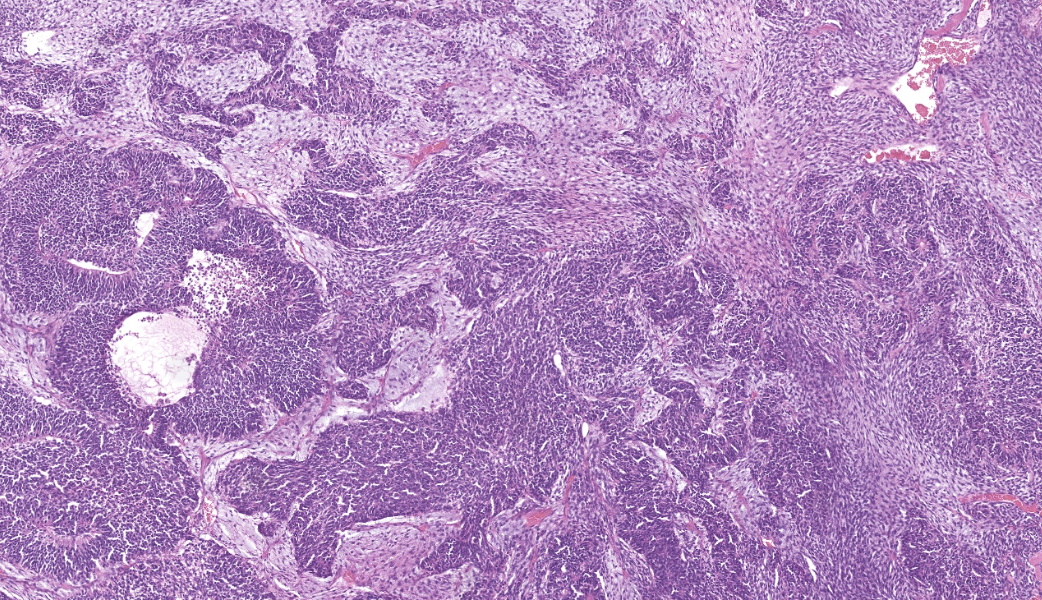

Expanding the anterior uvea, effacing the iris, and markedly expanding the suprachoroidal space is a densely cellular, unencapsulated neoplasm of neuroepithelial cells. Neoplastic cells are arranged in variably dense sheets and as palisading columnar cells surrounding a central lumen (Flexner-Wintersteiner rosettes) or surrounding eosinophilic fibrillar material (Homer-Wright rosettes) surrounded by collagenous and occasionally myxomatous stroma. Neoplastic cells are polygonal to fusiform, have a high nuclear to cytoplasmic ratio, and have distinct cell borders. The nuclei are round to ovoid, finely stippled, and have indistinct nucleoli. There are 16 mitoses in 10 high power fields and anisokaryosis is mild. The neoplastic cells are impinging upon the optic nerve, which has multifocal axonal degeneration and is infiltrated by a population of histiocytes, lymphocytes, and plasma cells, as well as scattered foci of hemorrhage. The retina has multifocal, disorderly components of viable photoreceptor and retinal ganglion cells, dense necrosis, glial scarring, and presumed Mueller cells. The retina is diffusely detached and lacks apparent retinal vessels. The retinal pigment epithelial cells have multifocally migrated through to the inner layers of the retina. The cortical lens fibers are moderately liquefied and homogenous and there is posterior migration of the lens epithelium, consistent with cataractous change. The corneal epithelium has marked, segmental ulceration and the outer corneal stroma in this area is mineralized with occasional breaks and is densely compact with fibrosis. Multifocally throughout the corneal stroma are areas of fibrosis, vascularization, and scattered neutrophils.Contributor's Morphologic Diagnoses:

Medulloepitheliomas classically present grossly as white to tan masses that fill the posterior chamber. The hallmark feature of primitive neuroectodermal tumors is the formation of rosettes. This tumor forms both Flexner-Wintersteiner rosettes (characterized by the formation of a central lumen) and Homer-Wright rosettes (characterized by the lack of central lumen and may surround eosinophilic fibrillar material).10 Importantly, the formation of both rosettes is found in other primitive neuroectoderm tumors and is not unique for medulloepitheliomas. Retinoblastoma is a similar primitive neuroectodermal tumor and must be differentiated histologically from medulloepitheliomas. In retinoblastomas, although they may occasionally have both types of rosettes, Flexner-Wintersteiner rosettes are often the dominant type. While retinoblastomas are common ocular tumors in young children, there are very few accounts of this diagnosis in veterinary species.5 Characteristically, rosettes in a medulloepithelioma are often large, multi-layered and lined by cuboidal cells arranged in a right angle to the lumen. There is pronounced neuroepithelial tubule formation, a distinguishing characteristic not found retinoblastomas. Medulloepitheliomas have been described more robustly in veterinary species, and the presence of large, multilayered, Flexner-Wintersteiner and Homer-Wright rosettes ultimately led to the diagnosis of medulloepithelioma in this case.